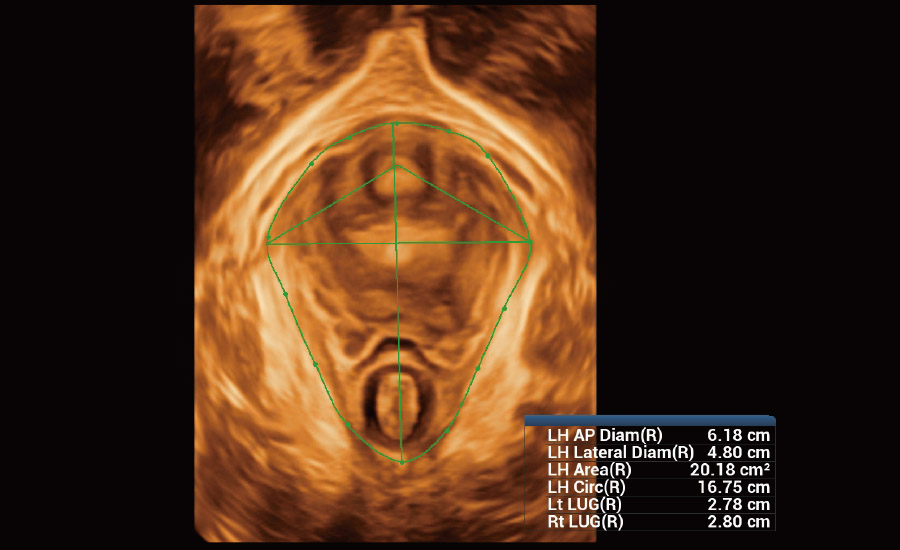

Urogynecology